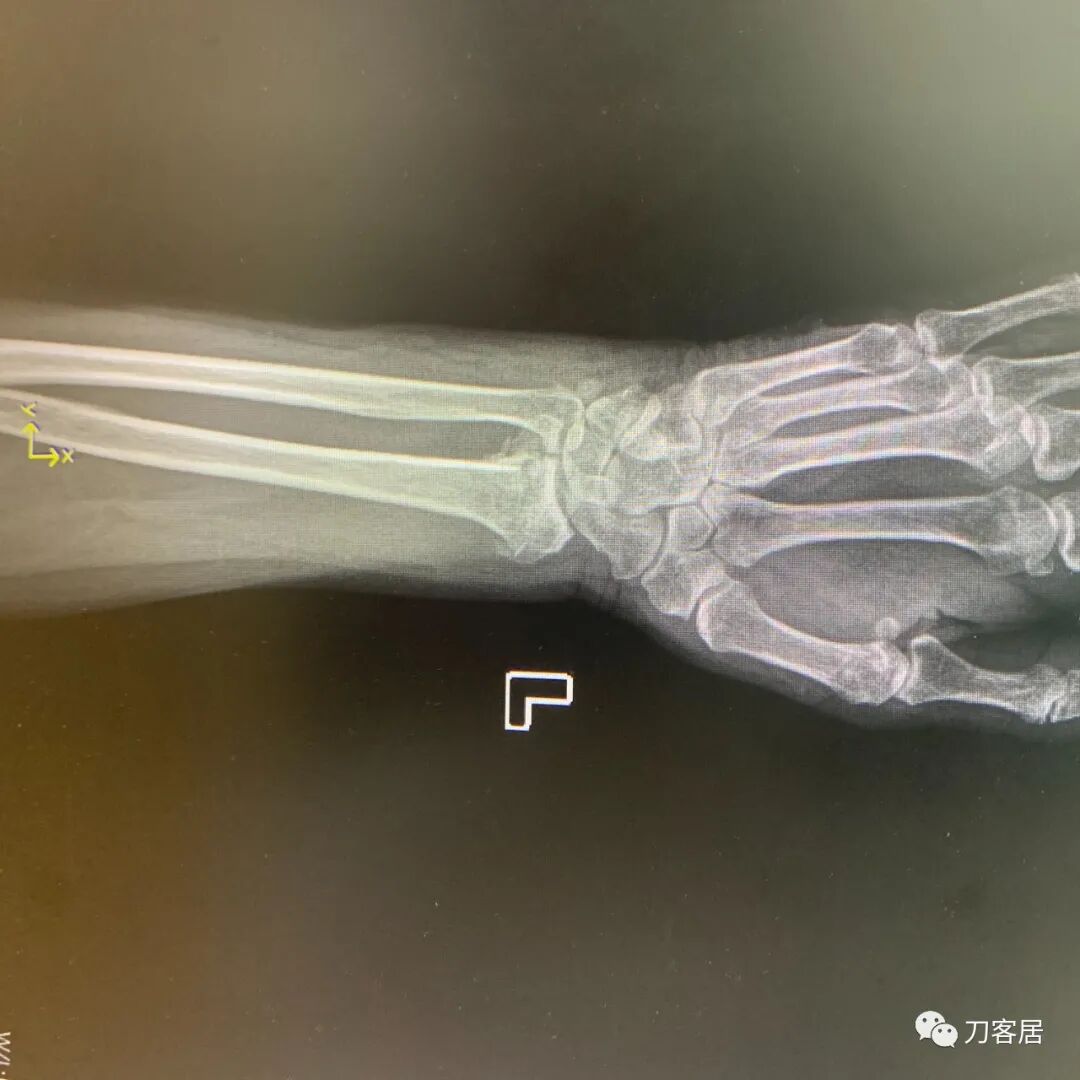

下面是这个6岁孩子,尺桡骨远端双骨折的术前及术后片子和外观照片。

1.  这是一个很简单的6岁儿童无移位的尺桡骨远端骨折。没有皮肤损伤,没有移位,没有骨折碎块儿。

2.  这个骨折处理起来也很简单,单纯的打石膏托或者中医的小夹板,或者正规的包括腕关节和肘关节的管型石膏外固定4周即可治愈该骨折。实在不行,如果这个孩子比较听话,不太调皮的话,用一本书,一个三角巾悬吊固定4周,都可以治愈该骨折。但是给这个患者用外固定架做了手术,而且桡骨远端的几颗克氏针距离骨折线太近,其中一枚克氏针进入到骨折间隙内。从这个术中图片来看,术者的外固定手术技术也有待于进一步的提高。毕竟术者应该还很年轻。从X线片来看,前臂及手的尺侧有不透光影,应该还使用了外固定石膏绷带托,而且我猜测应该是高分子的石膏绷带托,这个是纯属猜测,不一定是对的,不过如何解释前臂尺侧的不透光影呢?如果真是用了石膏绷带外固定的话,那为啥要做手术呢?外固定架术后就不该再用石膏绷带托辅助了。